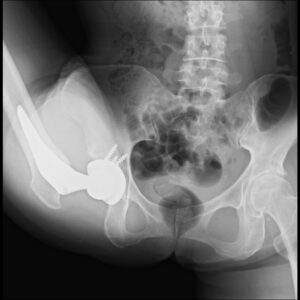

X線透視装置台でY字バランス

患者さんにご協力いただき、X線透視装置台の上でさまざまなバレエのポーズを取っていただいたところ、脱臼を懸念させるような動きは生じえないことがはっきりと観察できました。筋腱完全温存手術によって温存された筋肉が股関節の過度な動きを制限し、骨盤本来の動きが加わることで、大きな可動域を生み出していることが改めて認識できたわけです。